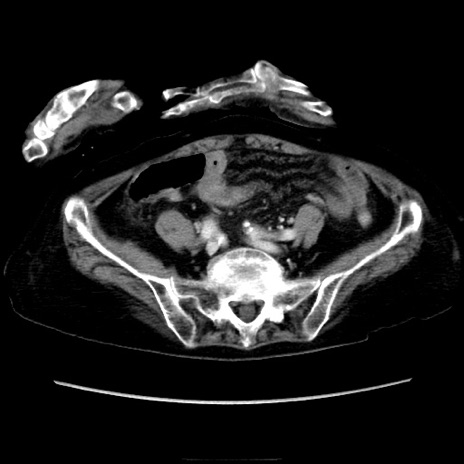

冠状断像

矢状断像